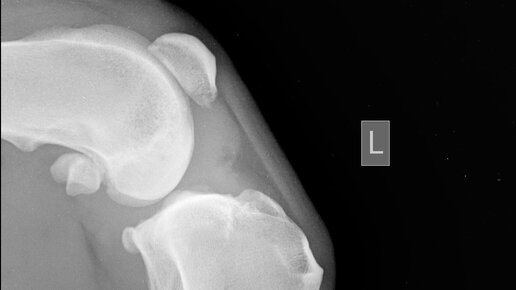

Ветеринарная ортопедия — раздел клинической ветеринарной хирургии, занимающийся изучением диагностики, лечения и профилактики патологий костно-мышечной системы, возникших в результате травм врожденных аномалий и осложнений при различных заболеваниях. Ветеринарная травматология — раздел клинической ветеринарии, изучающий различные повреждения опорно-двигательного аппарата животных. Ортопедия и травматология неразрывно связаны между собой. Ветеринарный врач-травматолог диагностирует и назначает лечение при травмах различной сложности, а также проводит реабилитацию животных после операций...